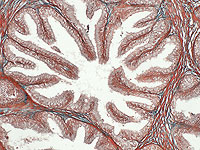

90% опухолей предстательной железы содержат микропластик

Внутри большинства опухолей предстательной железы ученые выявили частицы микропластика, причем их концентрация оказалась значительно выше, чем в здоровых тканях.